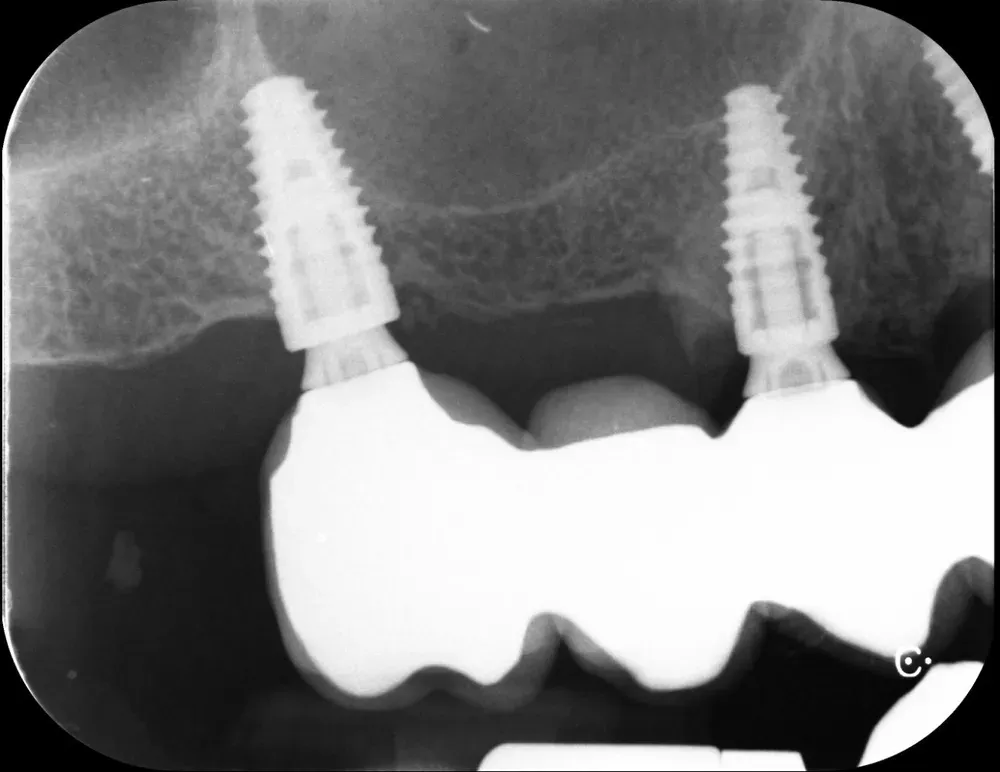

Di seguito potete vedere le foto intra-operatorie posteriori di destra e di sinistra:

Sul lato sinistro, l’atrofia dopo la rimozione dei denti e la rigenerazione era comunque meno grave e rientrava nell’ambito delle categorie S1-S2 CCARD. La prossima immagine è la CBCT della zona mascellare sinistra prima delle estrazioni.